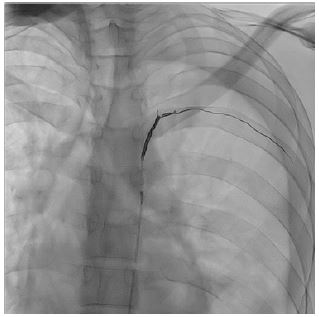

The patient underwent superselective arterial embolization of the involved intercostal artery (Figure 1). The procedure was successfully performed using microcoils (3 and 4 mm), obtaining immediate stop of bleeding (Figure 2). A left chest tube was placed and 1200 mL of blood were evacuated. The patient then underwent videothoracoscopic debridement to evacuate clots and some retained blood.

Figure 1: Angiographical embolization of intercostal pseudoaneurysm using microcoils.

Figure 2: Successful superselective arterial embolization.